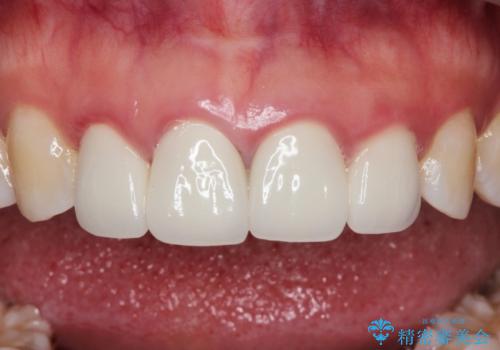

【精密根管治療+オールセラミッククラウン】より自然な前歯にしたい!

- 他院で治療した前歯が白すぎること、時々ズーンと痛むことを主訴に来院されました。

根っこの先端に病気も見つかったため、根管治療からやりかえて治療を行なっています。

被せ物の製作時は、患者さんと技工士さんが直接話をすることで、より満足度の高い治療を行うことができました。